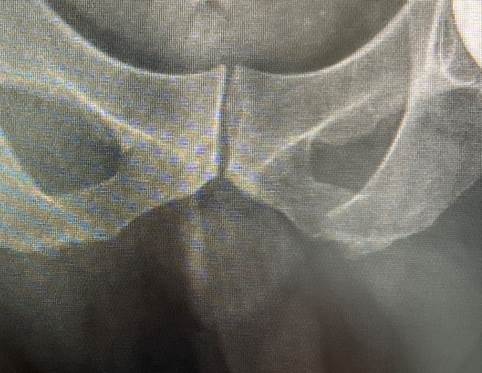

Hình chụp X-quang của bệnh nhân H.V.Đ. với chỏm xương đùi bị hoại tử.

Qua thăm khám, TS.BS Lê Trọng Phát, Trưởng khoa Chấn thương chỉnh hình, chẩn đoán anh Đ. bị chứng hoại tử chỏm xương đùi cả hai chân. Đây là hiện tượng lớp sụn bọc chỏm xương đùi không nhận đủ dinh dưỡng, lâu ngày bị thoái hóa và teo lại. Khi khớp không trơn, dính khớp, người bệnh sẽ cảm thấy đau khi cử động. Ngoài ra, anh Đ. còn mắc bệnh gout và vảy nến, gan thận bị ảnh hưởng do dùng thuốc lâu năm.